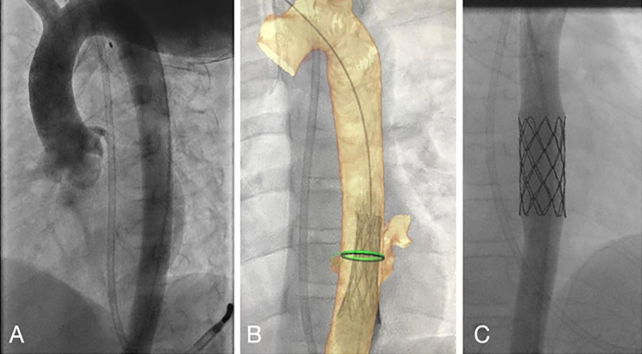

Helical Computed Tomography Angiography (CTA) of the chest was performed following the bolus intravenous administration of contrast. Circumferential esophageal wall thickening around the distal esophagus at the site of esophageal injury was seen. There was a linear arterial blush from the descending thoracic aorta into the posterior inflamed wall of the esophagus at the site of the esophageal injury. There was no mediastinal enhancement nor fluid. (Figure 2).

Figure 2: Helical Computed Tomography Angiography of the chest showing linear arterial blush from the descending thoracic aorta into the posterior inflamed wall of the esophagus at the site of the esophageal injury (green arrow).

Figure 2